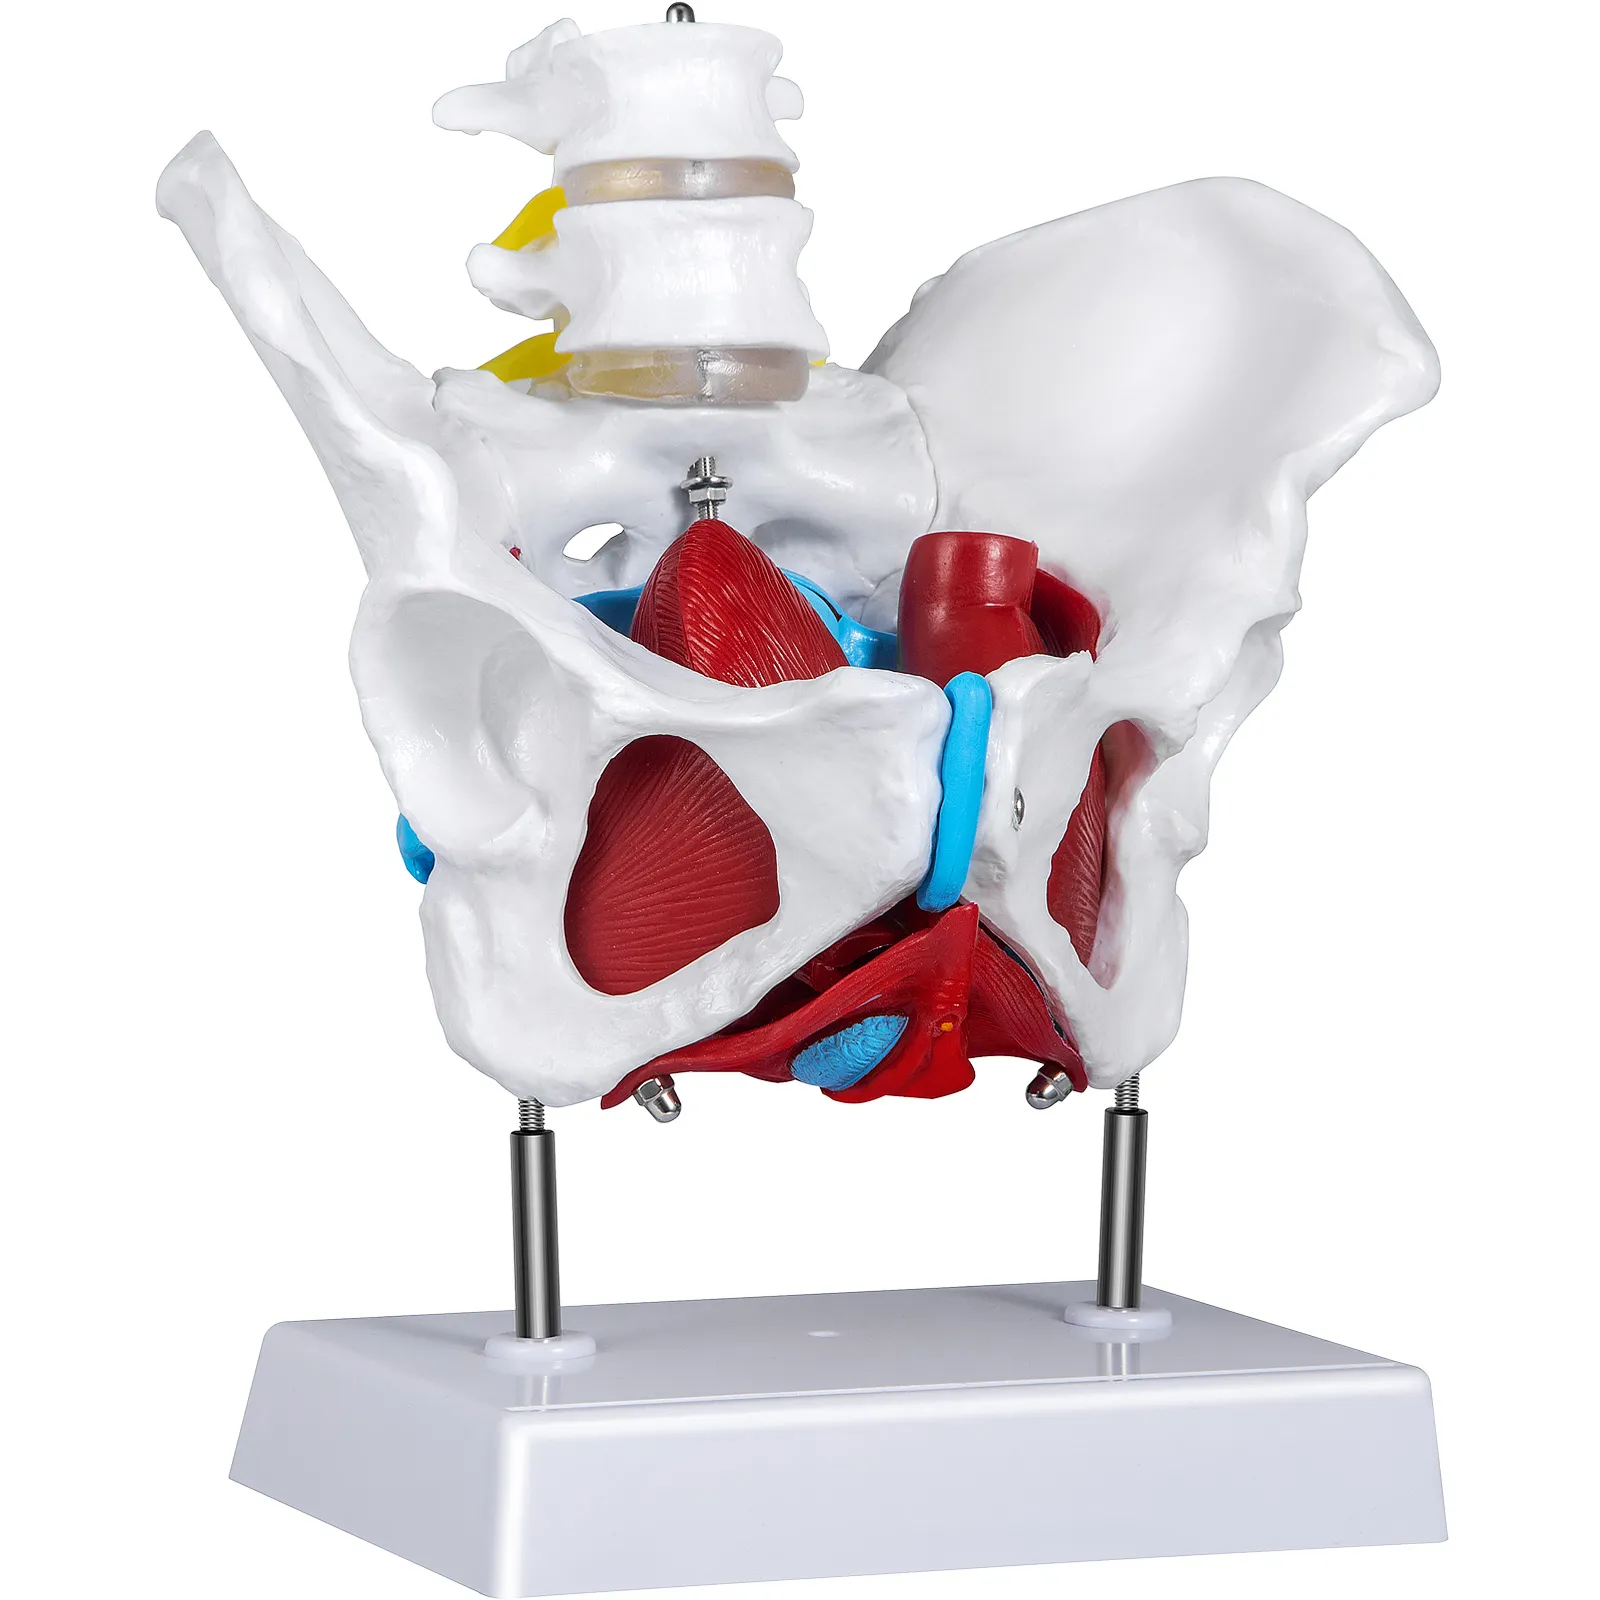

- 【VERWIJDERBARE STRUCTUUR】 - Het vrouwelijke bekkenmodel kan in vijf delen worden verdeeld, waardoor elk gebied van het bekken nauwkeurig wordt weergegeven en gelabeld met verschillende kleuren. Met het model kunt u de interne structuur van het vrouwelijke bekken vanuit alle hoeken observeren om het vrouwelijke bekken beter te leren kennen.

- 【NAUWKEURIGE MENSELIJKE SIMULATIE】 - Het model is ontworpen door experts op het gebied van bekkenonderzoek voor 100% nauwkeurige consistentie met de basisstructuur van het vrouwelijke bekken, in overeenstemming met de werkelijke grootte van het vrouwelijke bekken. Daarom is het levensgrote bekkenbodemmodel een ideale keuze voor anatomisch onderzoek van het vrouwelijk bekken.

Het model bevat 4 verwijderbare onderdelen en is een ongeveer levensgrote replica. Zoals alle anatomische structuren is er geen standaardmaat. Het perineum, baarmoeder, blaas en recta zijn gemakkelijk te verwijderen. Het bekkenmodel zal een geweldige aanvulling zijn op gynaecologische klinieken of studenten die gezondheidseducatie krijgen.

Vier Afneembare Onderdelen

Het model kan worden geopend en is eenvoudig te monteren en demonteren. Vanuit alle invalshoeken kunnen de studenten de vrouwelijke anatomie beter begrijpen.

Kleurgecodeerde Details

Het bekkenbodemmodel met spieren is met de hand beschilderd met verschillende kleuren om de verschillende delen en structuren van het bekken gemakkelijk te kunnen identificeren. U kunt de basiskennis van vrouwelijke bekkenconstructies moeiteloos door het model leren.

Realistisch Anatomisch Model

Voor de professionaliteit en nauwkeurigheid van het model is de grootte van het model hetzelfde als de grootte van het werkelijke vrouwelijke bekken, en elk onderdeel is realistisch. Het is speciaal ontworpen door vrouwelijke bekkenonderzoeksexperts voor onderzoek, leren en training van de bekkenanatomie.

Bekkenbodemmodel met Spieren

Het model bevat 4 verwijderbare onderdelen en is een ongeveer levensgrote replica. Zoals alle anatomische structuren is er geen standaardmaat. Het perineum, baarmoeder, blaas en recta zijn gemakkelijk te verwijderen. Het bekkenmodel zal een geweldige aanvulling zijn op gynaecologische klinieken of studenten die gezondheidseducatie krijgen.

Vier Afneembare Onderdelen

Het model kan worden geopend en is eenvoudig te monteren en demonteren. Vanuit alle invalshoeken kunnen de studenten de vrouwelijke anatomie beter begrijpen.

Kleurgecodeerde Details

Het bekkenbodemmodel met spieren is met de hand beschilderd met verschillende kleuren om de verschillende delen en structuren van het bekken gemakkelijk te kunnen identificeren. U kunt de basiskennis van vrouwelijke bekkenconstructies moeiteloos door het model leren.

Realistisch Anatomisch Model

Voor de professionaliteit en nauwkeurigheid van het model is de grootte van het model hetzelfde als de grootte van het werkelijke vrouwelijke bekken, en elk onderdeel is realistisch. Het is speciaal ontworpen door vrouwelijke bekkenonderzoeksexperts voor onderzoek, leren en training van de bekkenanatomie.